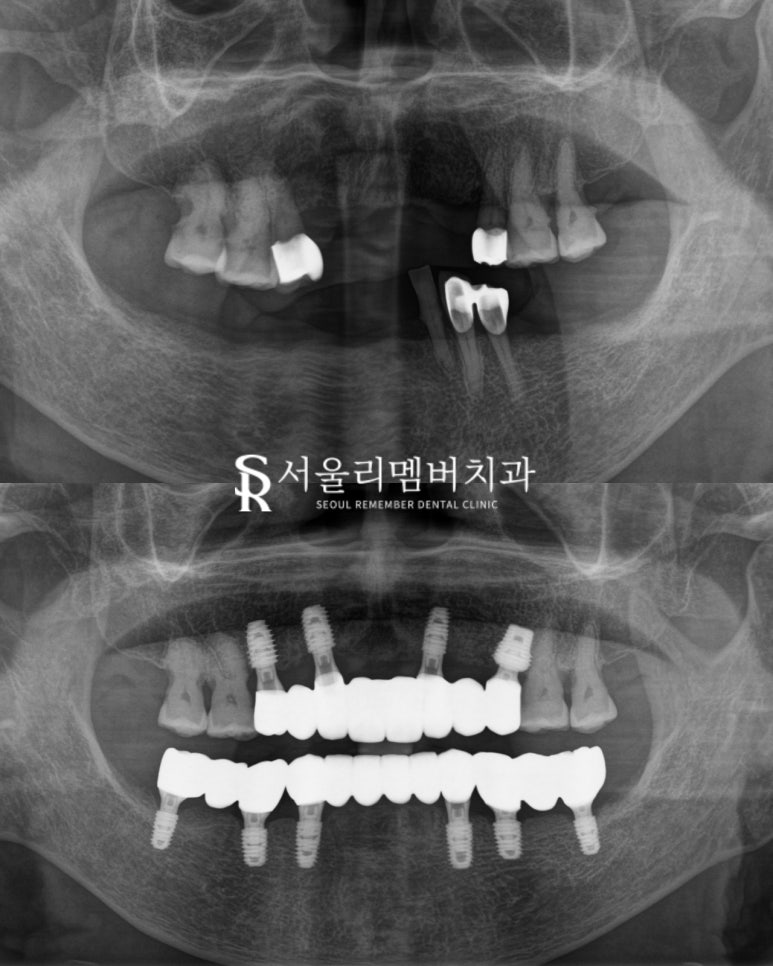

전체 임플란트 식립을 통해

개선 도와드리기로 했습니다.

신림역 치과 에서 시행하는

3D 디지털 분석 프로그램으로

사전에 컴퓨터 내에서 모의 시술을 진행합니다.

이때 계획한 위치와 각도에

맞추어 가이드를 제작하게 됩니다.

실제 수술에서 구강 내에

가이드를 장착하고 식립하므로

최소 절개를 통해 환자의 부기와 통증도 덜하답니다.

또 원하던 위치에 오차 없는 수술을 할 수 있는 것이죠.

픽스처를 식립했습니다.

평균적으로 3~4개월 정도

픽스처와 골 유착하는 시간을

안전하게 가지고 있습니다.

위(전), 아래(후)